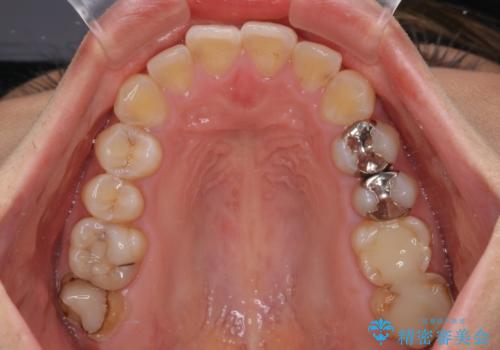

- 口元の突出感と奥歯のむし歯を気にして来院された患者様です。

奥歯の虫歯は事前に矯正治療用の仮歯に置き換えて矯正治療を行い、装置除去後にセラミッククラウンにて補綴治療を行うこととしました。

通常は上下左右の第一小臼歯4本を抜歯することになりますが、左側下顎の第二小臼歯は既に根管治療をされており、予後が良くないとのことでこの歯を抜歯し、ワイヤー装置にて矯正治療を行うこととしました。